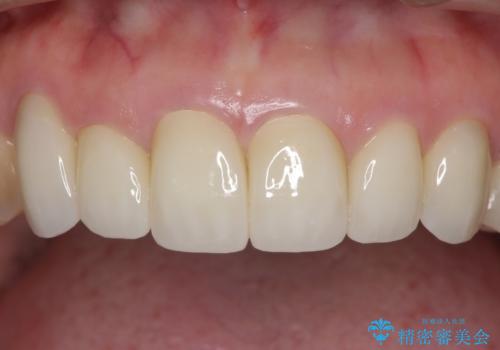

- 下顎の前歯に激痛を覚えて来院された患者様です。

取り急ぎ下顎前歯数歯の根管治療を、銀座しらゆり歯科医院長の林先生にお願いし、それ以外に気になっている、不自然な色調のクラウン、金属部分が見えてブラッシングがしにくいインプラント補綴、口元の突出感、出血のしやすい歯周ポケットなど、全てを解決するための治療を行うこととしました。

期間と費用はかかりましたが、気になっていた部分全てを改善でき、患者様には大変満足していただきました。